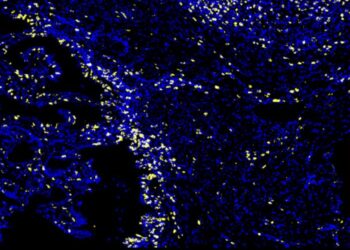

Lymphomas represent a complex group of malignancies derived from cells of the immune system, predominantly affecting lymphoid organs such as...